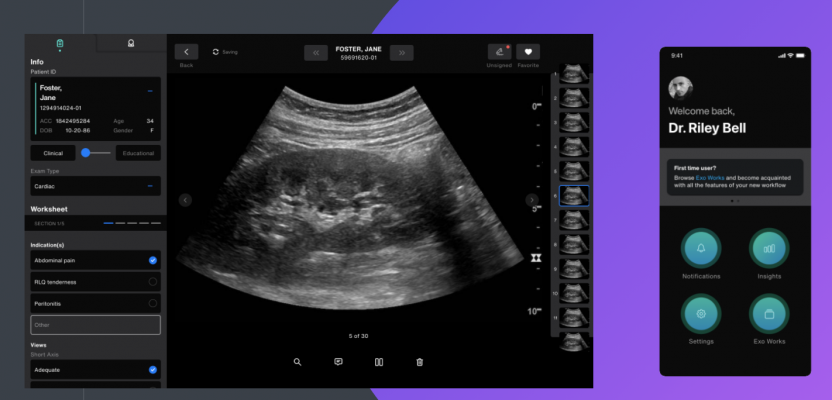

Exo’s medical imaging ecosystem includes its proprietary point-of-care ultrasound workflow solution, Exo Works. It solves decades-long workflow issues by streamlining exam review, documentation and billing in one platform — in under 60 seconds.The software works with nearly all point-of-care ultrasound devices and securely connects to the most common EMR and PACS systems used in hospitals to house imaging and communications. The ease of connectivity finally makes interoperability a reality and disconnected ultrasound processes a thing of the past.

The combination of Exo’s handheld ultrasound device and Exo Works will seamlessly blend an entire medical imaging ecosystem to perform flawlessly in one of the most demanding real-world applications of technology, while unlocking numerous applications across a wide swath of medical care. Uses such as predictive diagnostics could influence patients to make better choices and adopt healthier lifestyles prior to a confirmed diagnosis. Remote quality assurance and credentialing could allow experienced providers at different institutions to review and approve medical imaging. Ultrasound scans via telemedicine would enable patients at home to be sent a probe and guided through a scan by an experienced provider.